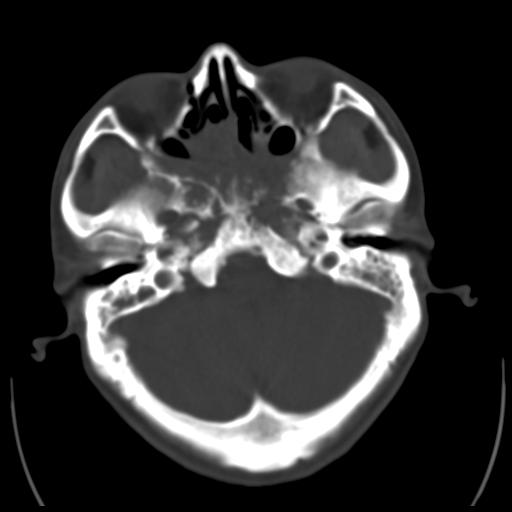

35m 鼻子时不时流血,头及右侧面部痛,颈部淋巴结未见明显大

软组织窗

考虑鼻咽癌侵犯颅底并突入右侧鼻腔;双侧中耳乳突炎。

蝶窦,后组筛窦及鼻咽部团块状软组织影,骨壁破坏,病变较广泛。考虑恶性肉芽肿。建议活检。

考虑中线肉芽肿(鼻硬结病),次之tb或真菌感染性肉芽肿,病变形态不像肿瘤,建议增强及活检。

蝶窦,后组筛窦及鼻咽部团块状软组织影,骨壁破坏,病变较广泛。考虑炎性肉芽肿性病变可能。建议活检。